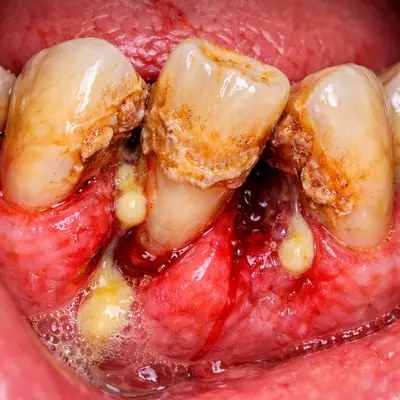

دندان عقل در انتهای دهان قرار دارد و بهخوبی تمیز نمیشود؛ همین موضوع احتمال گیر غذایی، التهاب لثه و عفونتهای مکرر را بالا میبرد. عفونتهای تکرارشونده میتوانند به دردهای مداوم و حتی دردهای مزمن فک منجر شوند.

با گذشت زمان، فشار دندان عقل به دندانهای کناری میتواند باعث آسیب به دندان مجاور، پوسیدگی بیندندانی یا تحلیل استخوان موضعی شود؛ مشکلاتی که درمان آنها ساده نیست.

اگر علائم عفونت یا التهاب وجود دارد، اول آن را جدی بگیرید.

درد ضرباندار، بوی بد دهان، تورم لثه یا ترشح میتواند نشاندهنده التهاب یا عفونت باشد. در چنین شرایطی ممکن است ابتدا کنترل عفونت و سپس جراحی انجام شود تا هم بیحسی بهتر اثر کند و هم تجربه درمان آرامتر شود.